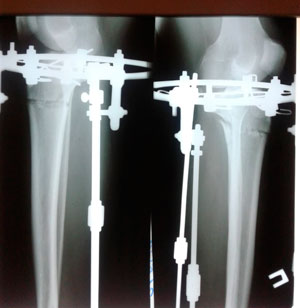

Дата операции - 12.07.2019г.

Дата снятия аппаратов - 17.10.2019г.

Срок сращения - 95 дней.